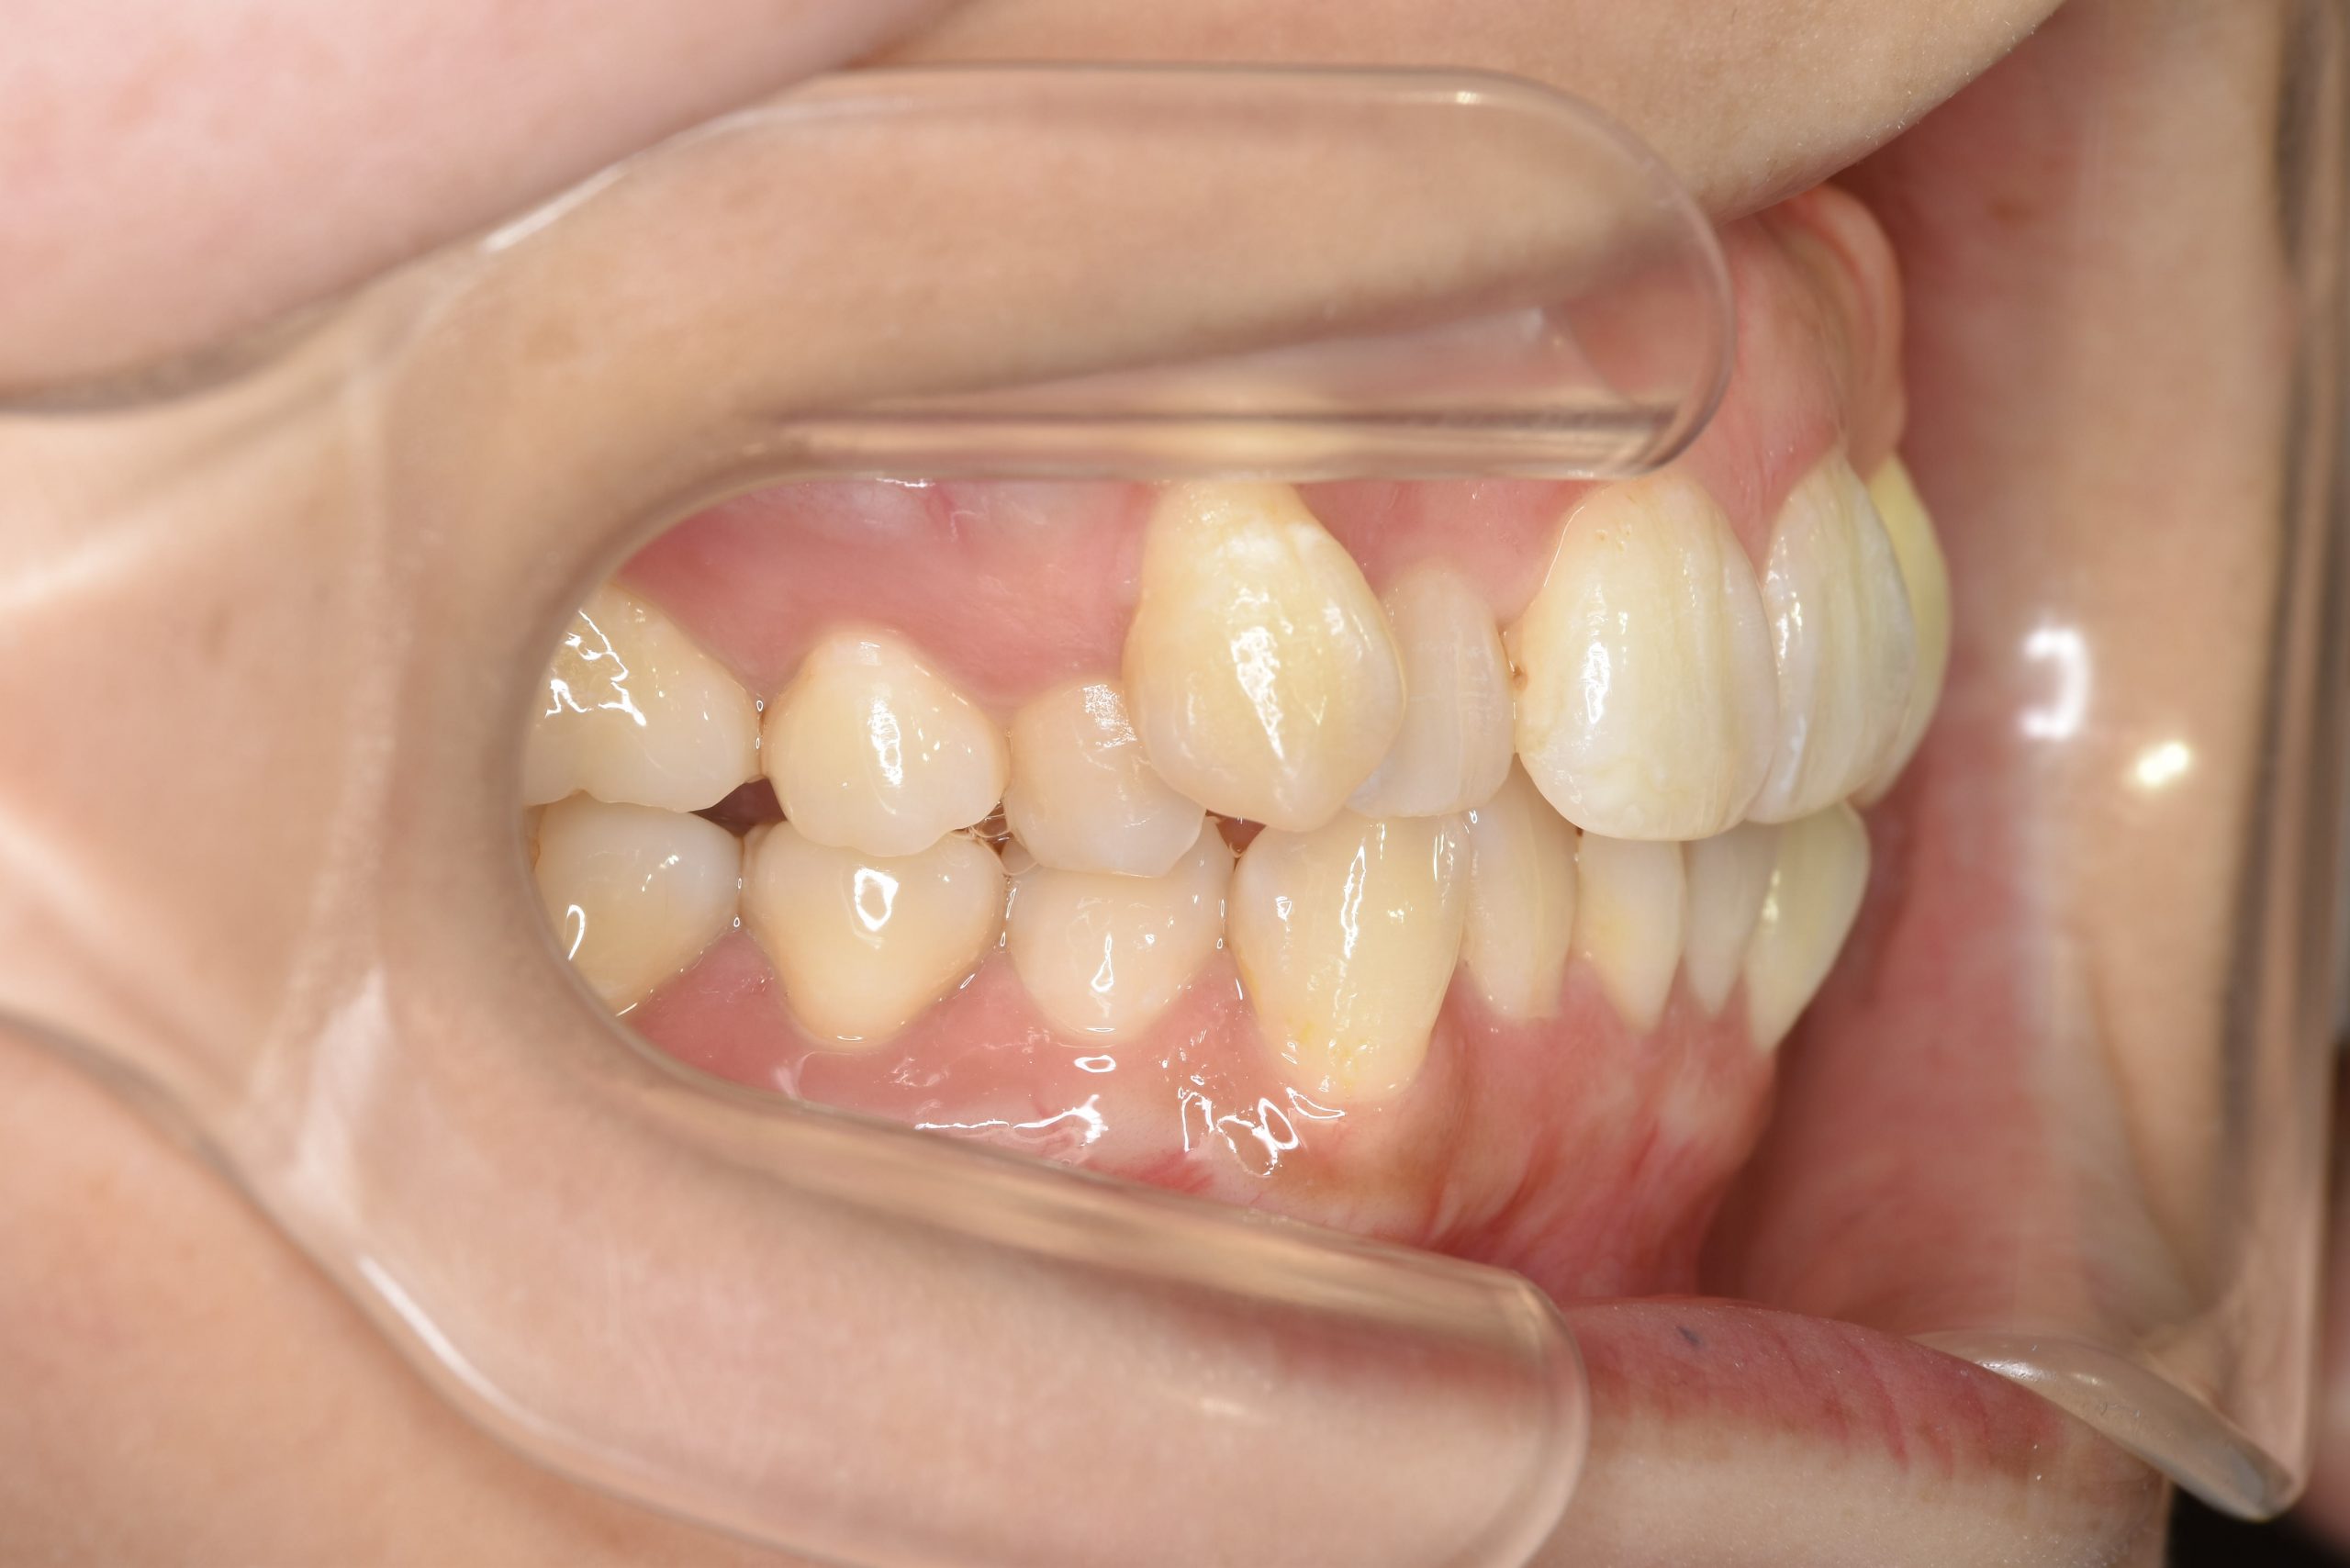

アフター

施術内容 MSEと下顎リンガルアーチを用いて上下顎骨を拡大した。

その後上顎3・4番を抜歯しマルチブラケット装置とミニインプラントを用いて

歯牙を配列した。良好な咬合を獲得した。

治癒期間 1年8か月間